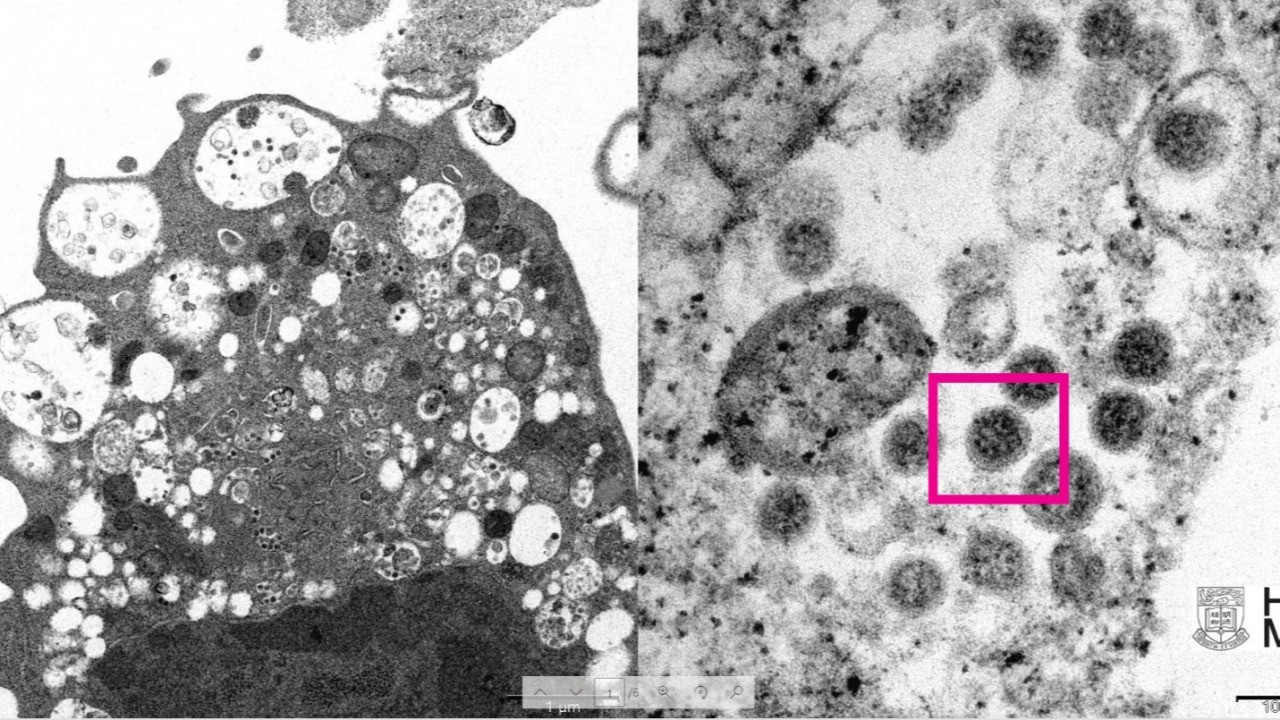

HKUMed’den yapılan açıklamada, araştırmacılar tarafından SARS-CoV-2 virüsünün Omicron varyantının elektron mikroskobu görüntüsünün ortaya çıkarıldığı belirtildi. Üniversite tarafından yayınlanan fotoğrafın solunda, küçük siyah viral partiküller içeren şişmiş veziküllerle hücre hasarını gösteren, SARS-CoV-2 Omicron varyantı ile enfeksiyondan sonra bir maymun böbrek hücresinin (Vero E6) düşük büyütmeli elektron mikrografının yer aldığı ifade edildi. Fotoğrafın sağında ise yüzeylerinde korona şekilli sivri uçlara sahip viral partikül kümelerini gösteren enfekte bir Vero E6 hücresinin yüksek büyütmeli elektron mikrografının yer aldığı belirtildi.